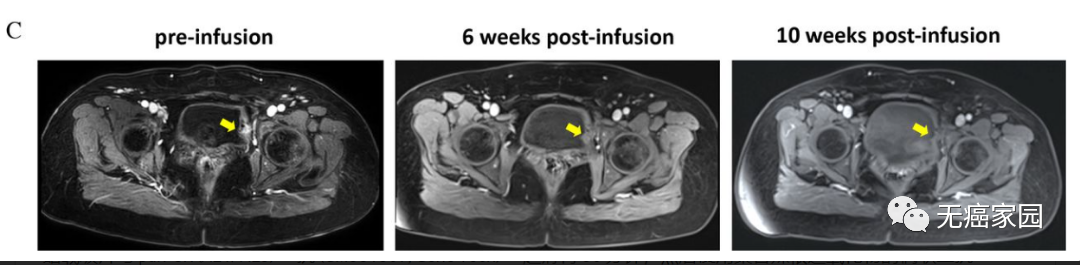

TIL输注6周后,T1WI显示病灶明显缩小(黄色箭头)。根据实体瘤反应评估标准 v1.1 (RECIST),患者在输注后 10 周确认完全缓解(图 1C)。

从左到右依次为输注前,输注后6周,输注后10周的影像图

2022年2月17日,我国医学研究人员刊登在《JITC》上的一篇案例报告中,对一名患有复发性宫颈癌并伴有膀胱转移的患者采用自体肿瘤浸润淋巴细胞(TIL)输注和改良的淋巴细胞清除方案进行治疗的I期临床试验结果进行报道。切除组织的特征表明肿瘤区域内浸润的淋巴细胞有限。值得注意的是,输注后的 IL-2 注射也从治疗中移除。患者在 TIL 输注后 10 周达到完全缓解,治疗期间不良反应较少。